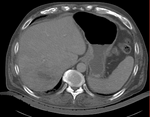

original unregistered

rigid registered affine registered

nonrigid registered (7x7x7 BSpline unmasked) nonrigid registered (7x7x7 BSpline masked)